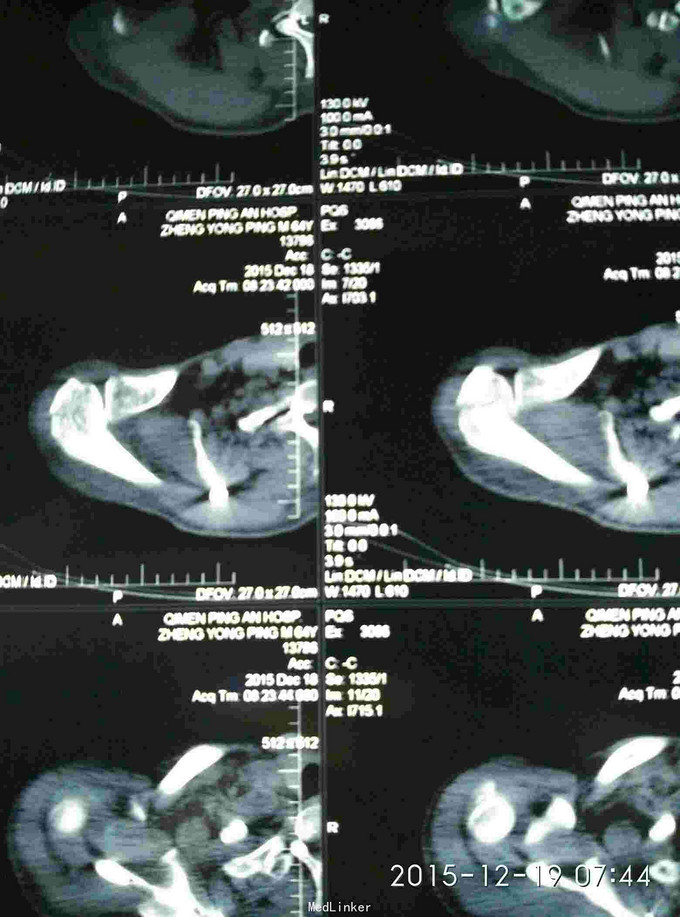

右肩峰及肩胛骨骨折

骨折 肩峰骨折 肩胛骨骨折

外伤致右胸疼痛及右肩疼痛,活动受限1天入院。去年右肩胛骨骨折在外院行切开复位内固定术。

胸廓挤压试验阳性,右肩峰压痛阳性,右肩主动活动受限,外展约30度。x片及CT示右肩峰骨折及肩胛骨骨折,右第6.7.8.9肋骨骨折。

右肩峰骨折,右肩胛骨骨折,右第6.7.8.9肋骨骨折